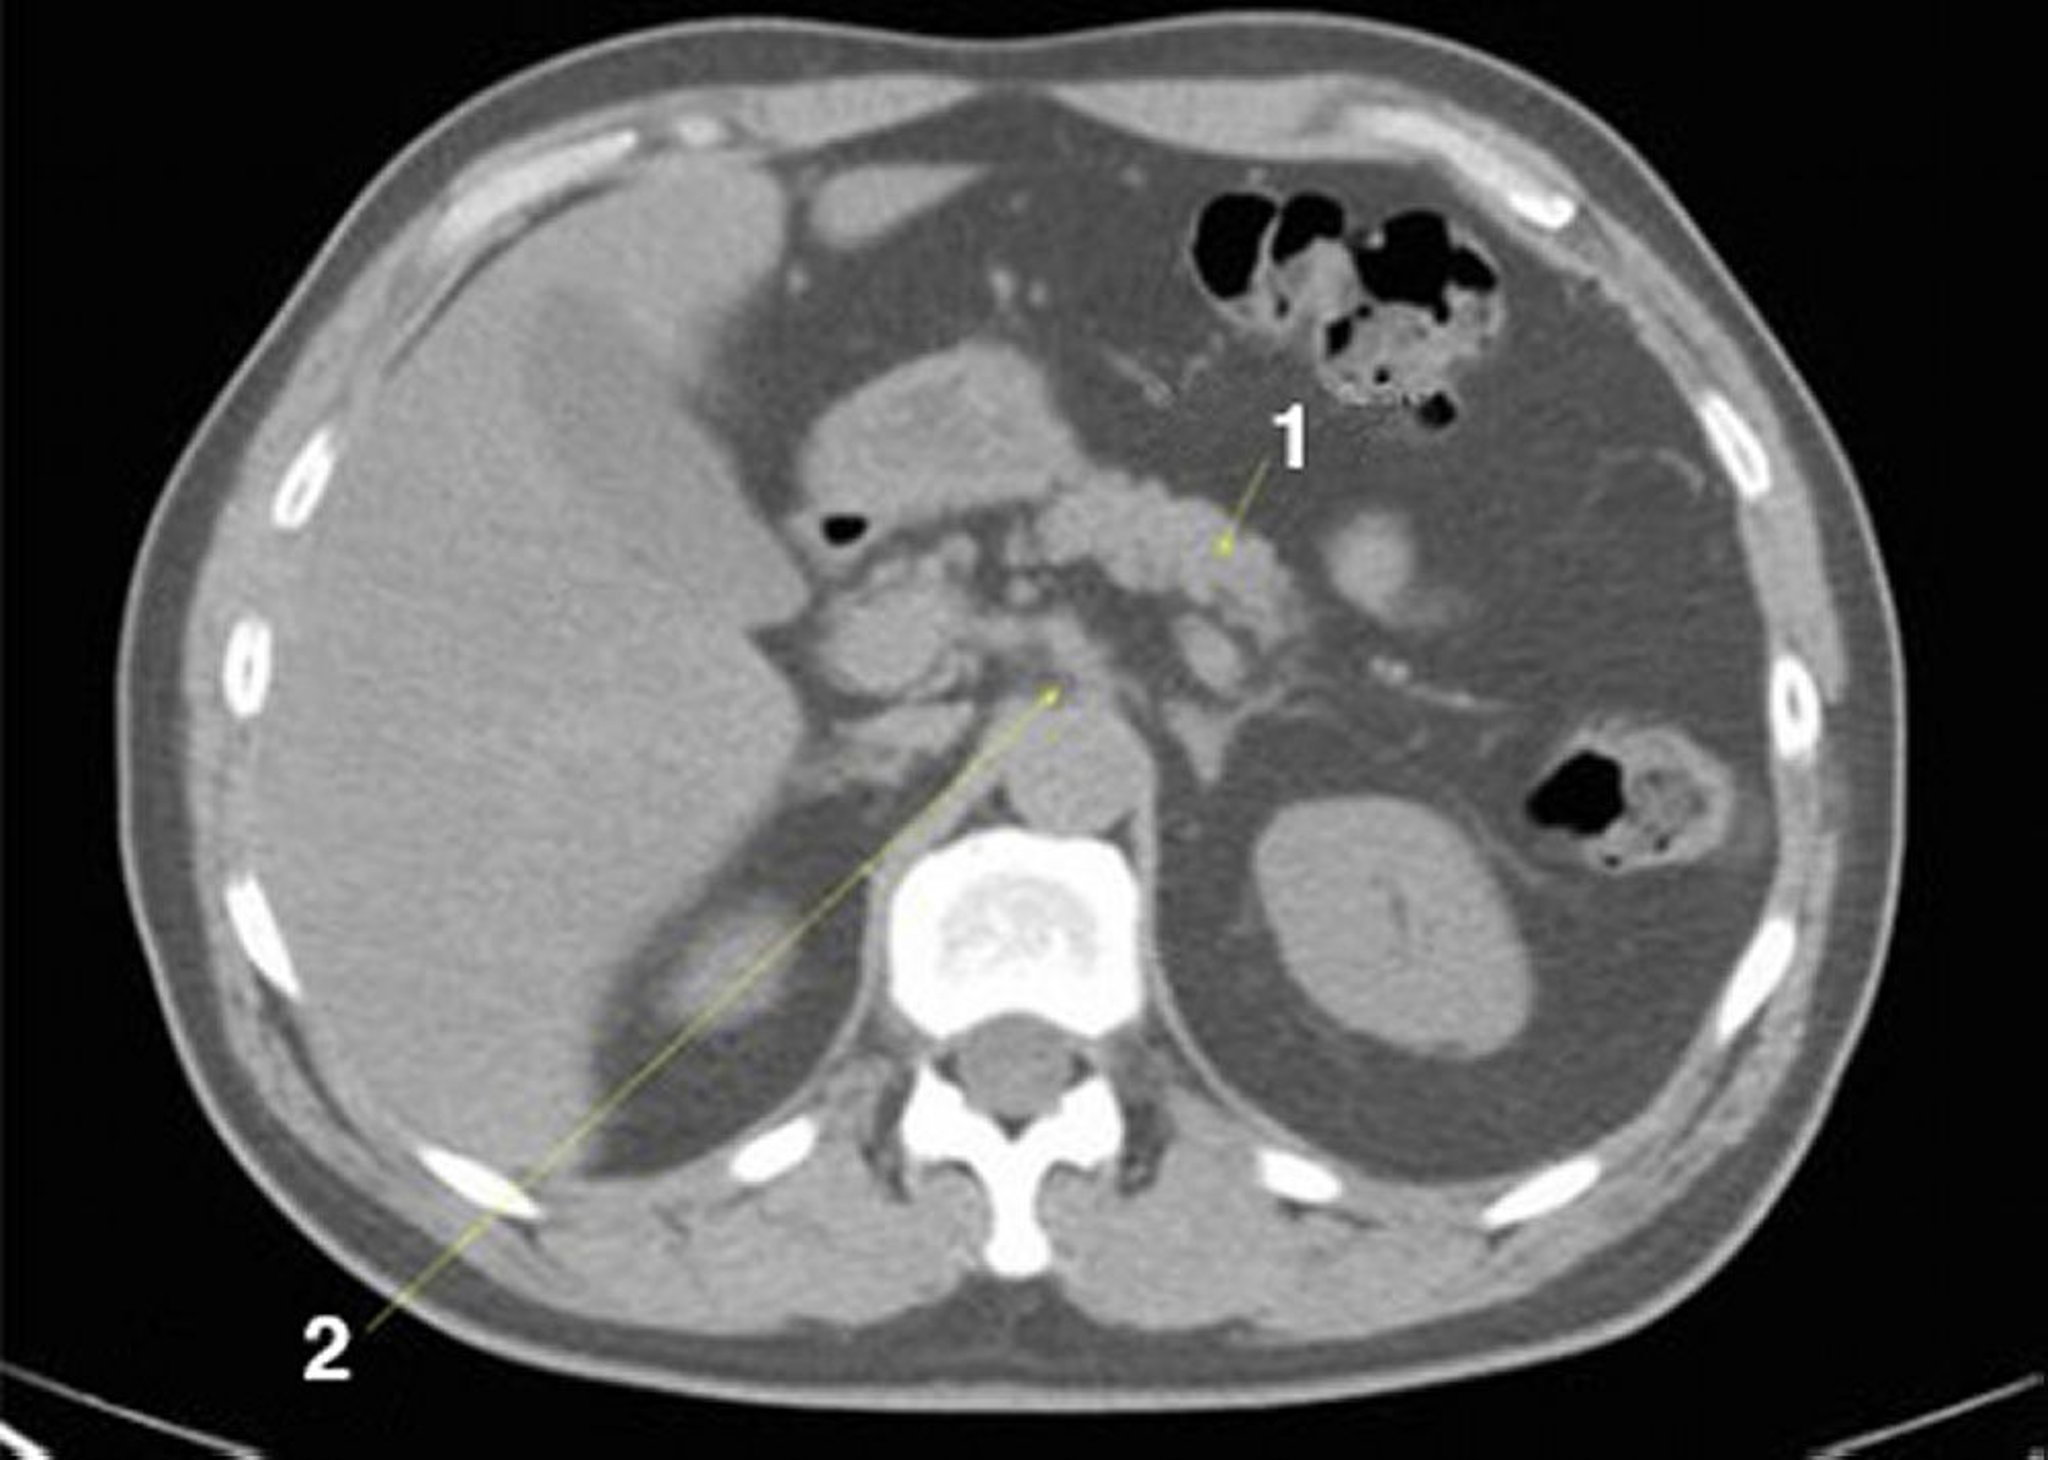

Noncontrast CT Scan of the Abdomen and Pelvis Showing Normal Anatomy (Slide 9)

1 = pancreas; 2 = celiac axis.